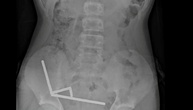

Chirurgen in Neuseeland haben dutzende Magneten aus den Gedärmen eines 13 Jahre alten Jungen entfernt. Der Junge habe bis zu 100 Hochleistungsmagneten heruntergeschluckt, die er